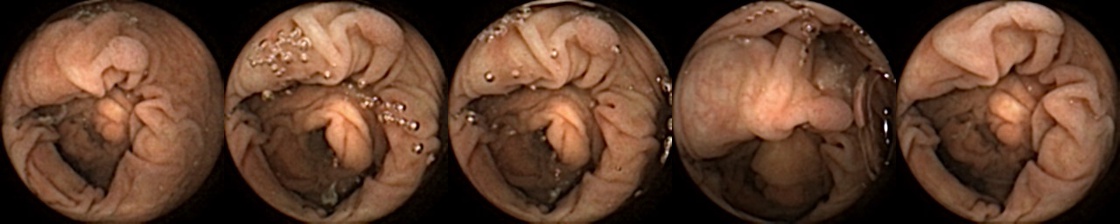

Similarly, we consider examples for the MIV model based on SimCLR pretraining using the pretrained ConvNext backbone in Figure 4. The model has a test accuracy of 86.26% for DBA L1 with 2 heads. Here we note again a similar trend by looking at the True Positive and False Negative examples as observed before, where a significant difference in the query image when compared with the target images can lead to a failure to identify the same polyp images in the five examples. A look at the False Positive examples affirms that the task remains challenging, as evidenced by the model’s occasional misclassifications in ambiguous cases.

True Positive False Negative

False Positive True Negative

Figure 4: True Positives (Pred = true, Label = true), False Negatives (Pred = false, Label = true), False Positives (Pred = true, Label = false),True Negatives (Pred = false, Label = false) for the DBA L1(h=2) model applying SimCLR using the ConvNeXt backbone. In each row, the leftmost image is the query and the 4 images to the right of each query are the target images.